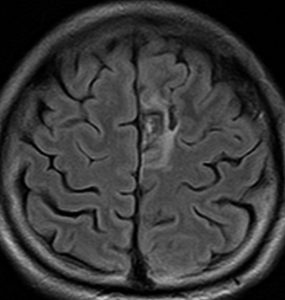

退形成性星細胞腫 グレード3の膠芽腫としての再発例

左上前頭回のびまん性グリオーマ diffuse glioma です。手術でほぼ全摘 gross total removalして54グレイの放射線治療とテモゾロマイド化学療法をしました。病理診断は,oilg 2陽性,1p/19q染色体の欠失はない退形成性乏突起星細胞腫 グレード3とされました。全体的にはグレード2であるとの病理医の意見もありましたし,当時は北大病院でもIDHの正確な分子病理診断は行われていませんでした。

5年後です。上前頭回の病巣は落ち着いていましたが,初回にはなかったはずの場所,脳梁前方に急激な再発増大を生じました。また手術で全摘出 gross total removalして,かなり絞った領域に60グレイの放射線治療とテモゾロマイド,アバスチンの投与をしました。病理診断は,IDH wild-tpye, 1p/19q non-codel, MIB 40%, ATRX positive, MGMT negativeの膠芽腫でした。

その後またしばらく寛解継続できました。